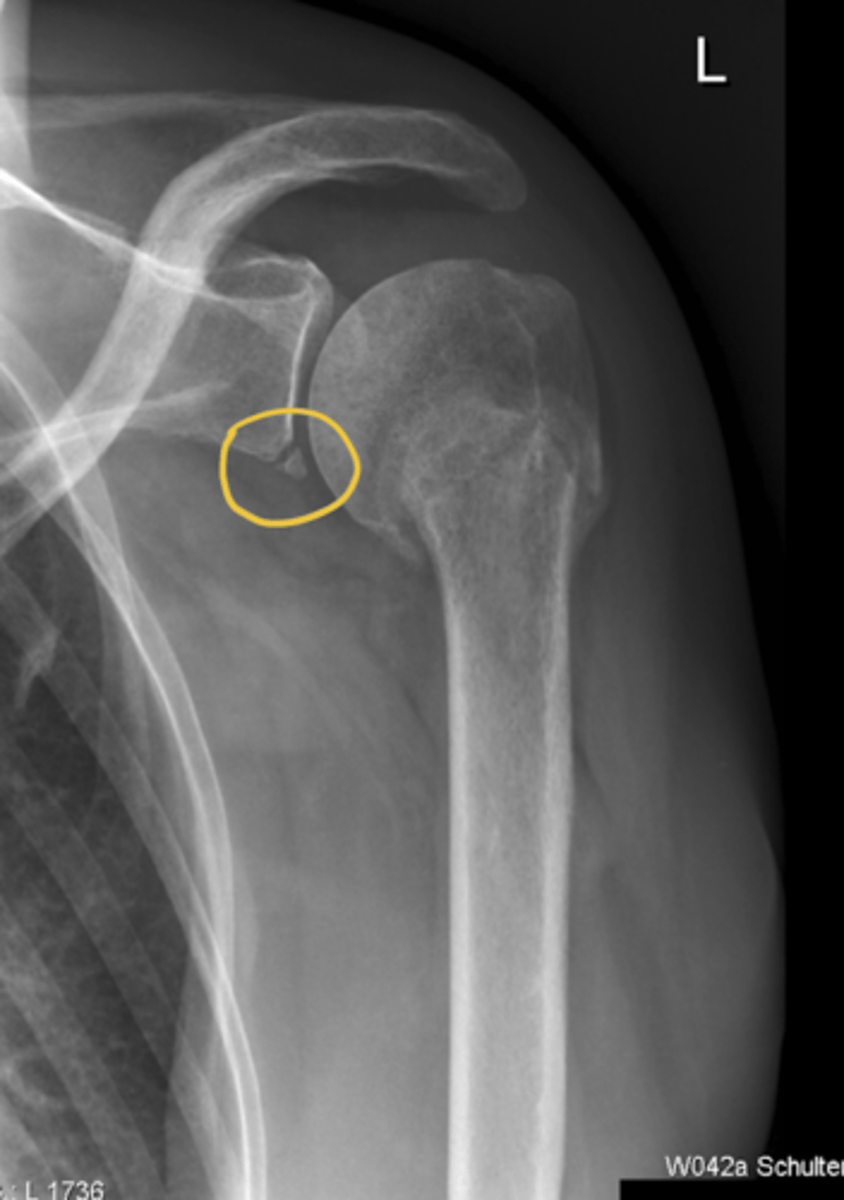

________: can occur when dislocated humeral head compresses border of glenoid (ex: from an anterior/inferior dislocation)

Bony Bankart lesion (i.e., an avulsion of the capsulolabral tissue from the anteroinferior glenoid rim)